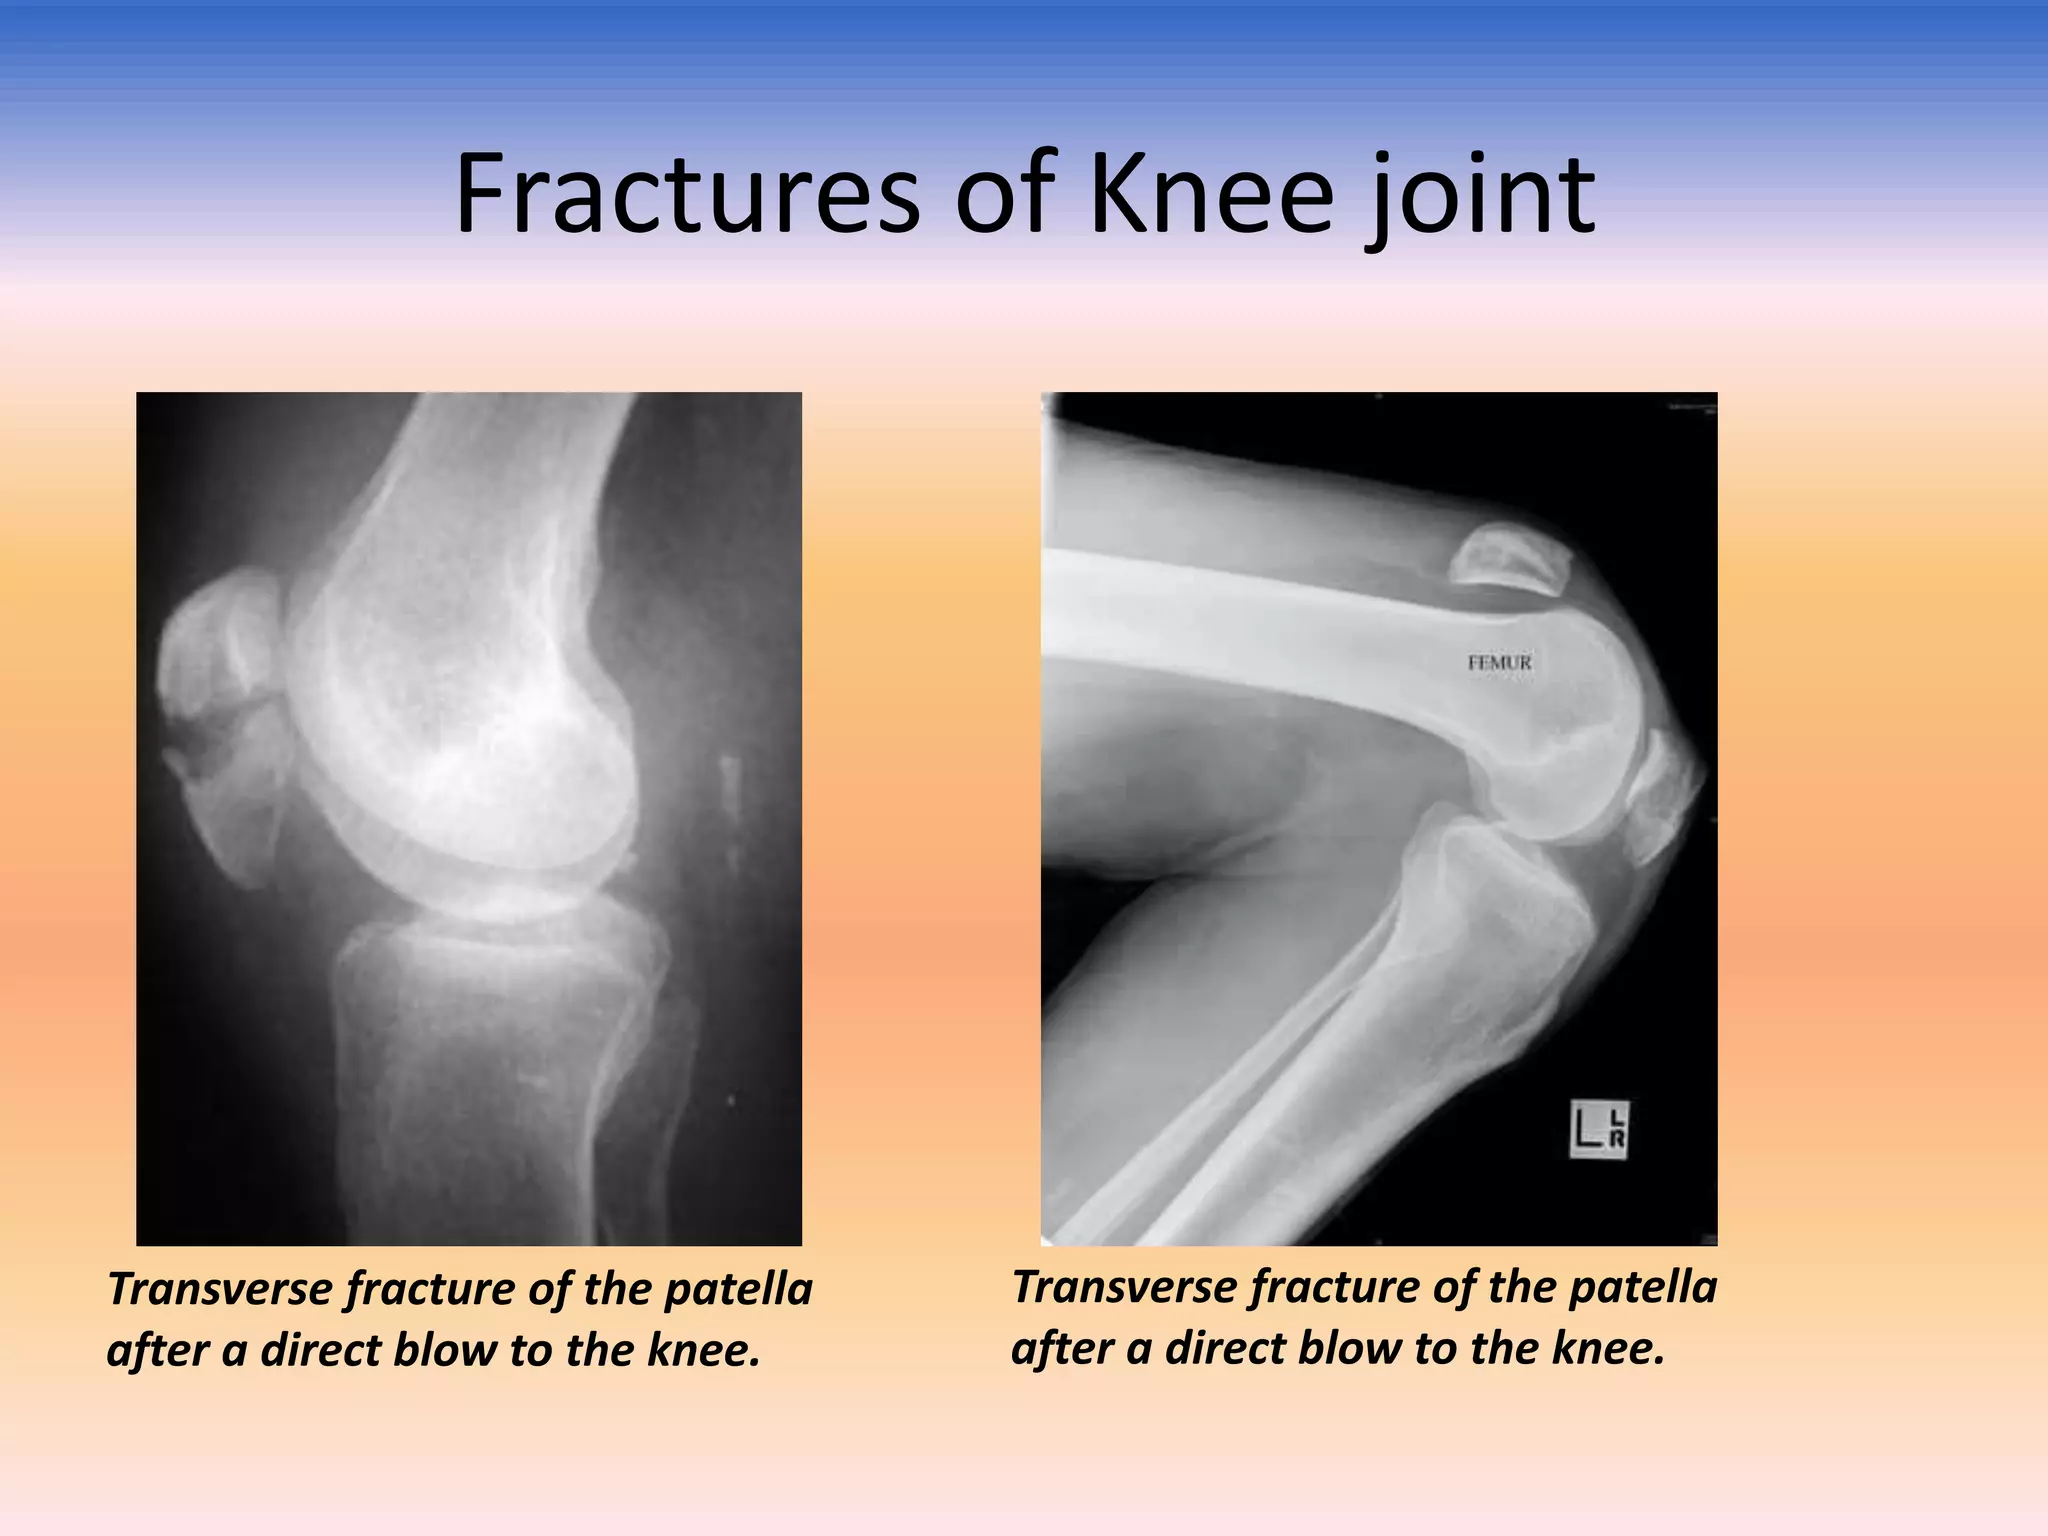

Fractures of Knee joint

Transverse fracture of the patella

after a direct blow to the knee.